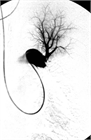

病態

1. 急性肺塞栓症とは、静脈系にできた塞栓子(大部分が血栓)が肺動脈を閉塞させ、その結果、肺動脈の血流が障害されて呼吸や循環に異常を来した状態をいう。